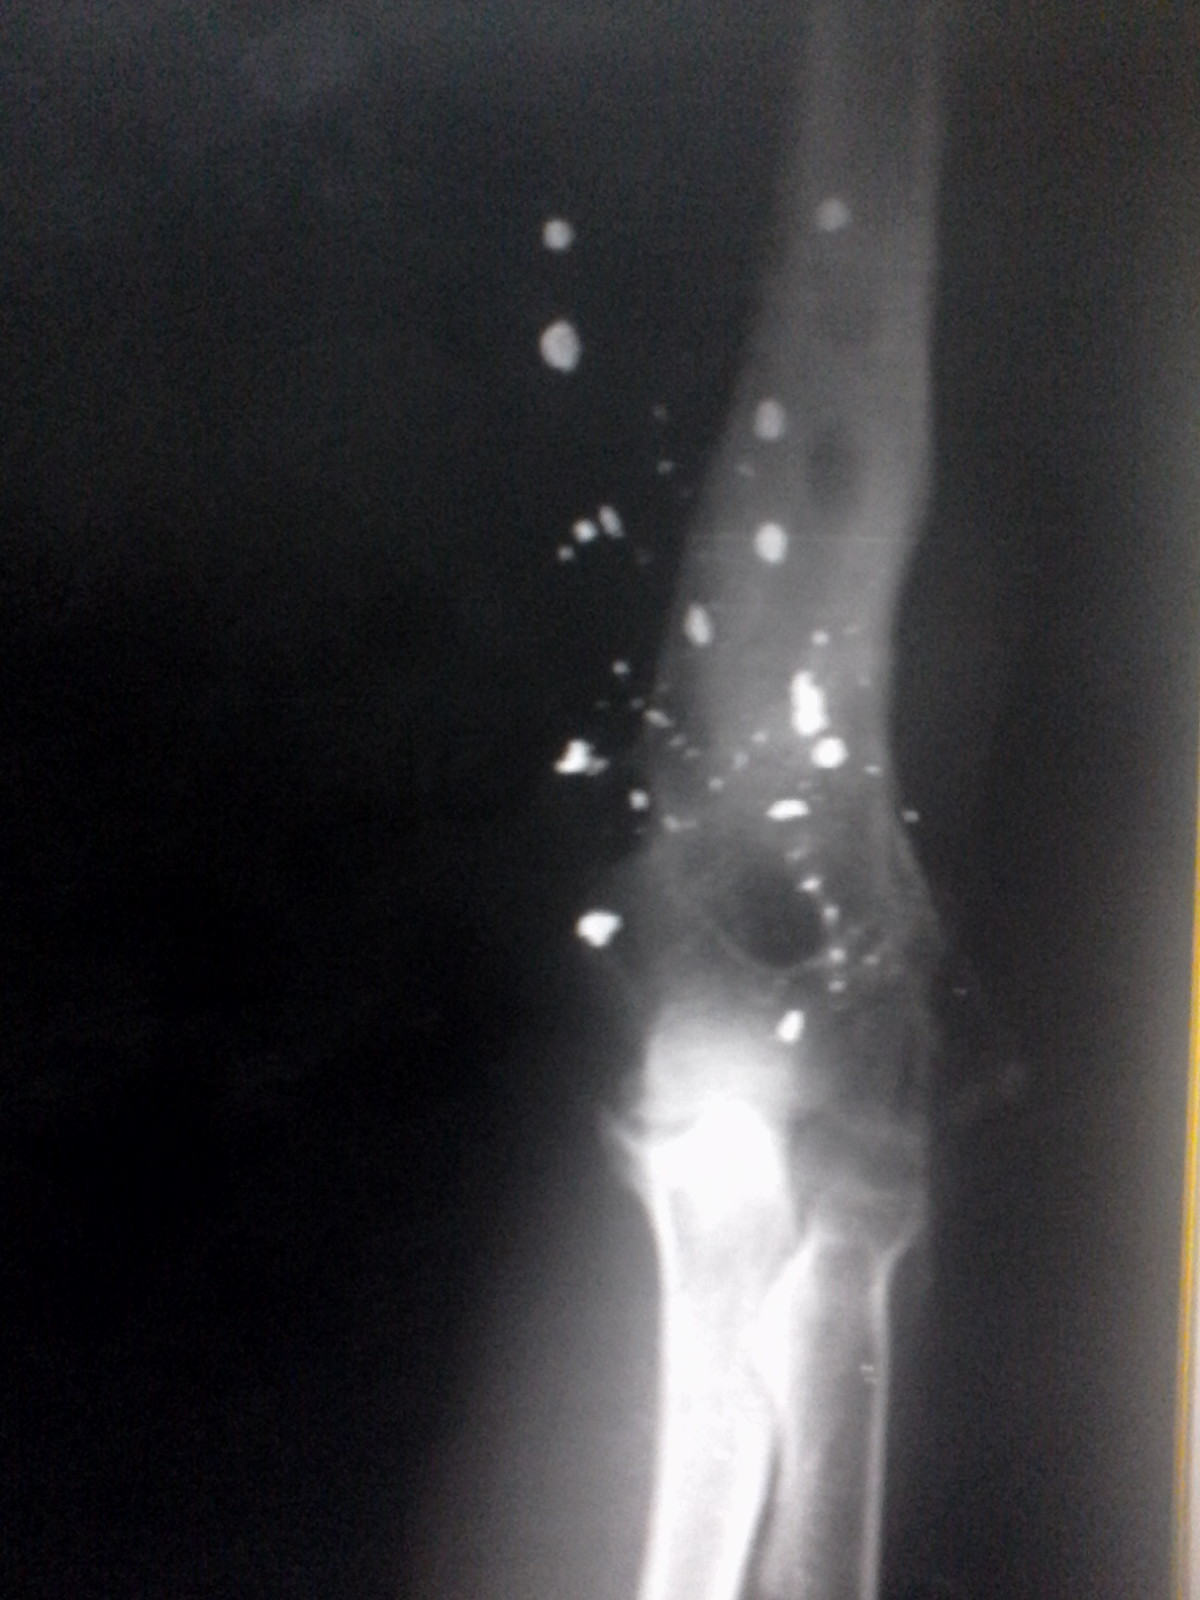

En las siguientes imágenes pueden observarse un par de estudios que fueron realizados a un paciente masculino de aproximadamente 40 años de edad, el cual acude a la sala de rx del Hospital Central Dr Placido D Rodriguez con el fin de realizarse un rx de codo en dos proyecciones. El estudio fue remitido al paciente para un control anual luego de haber sufrido un grave accidente.

Dicho paciente tuvo un accidente automovilístico en el cual pedazos de plomo se alojaron en su piel y músculos quedando allí gracias a las propiedades del cuerpo humano para adoptar materiales metálicos en su sistema.